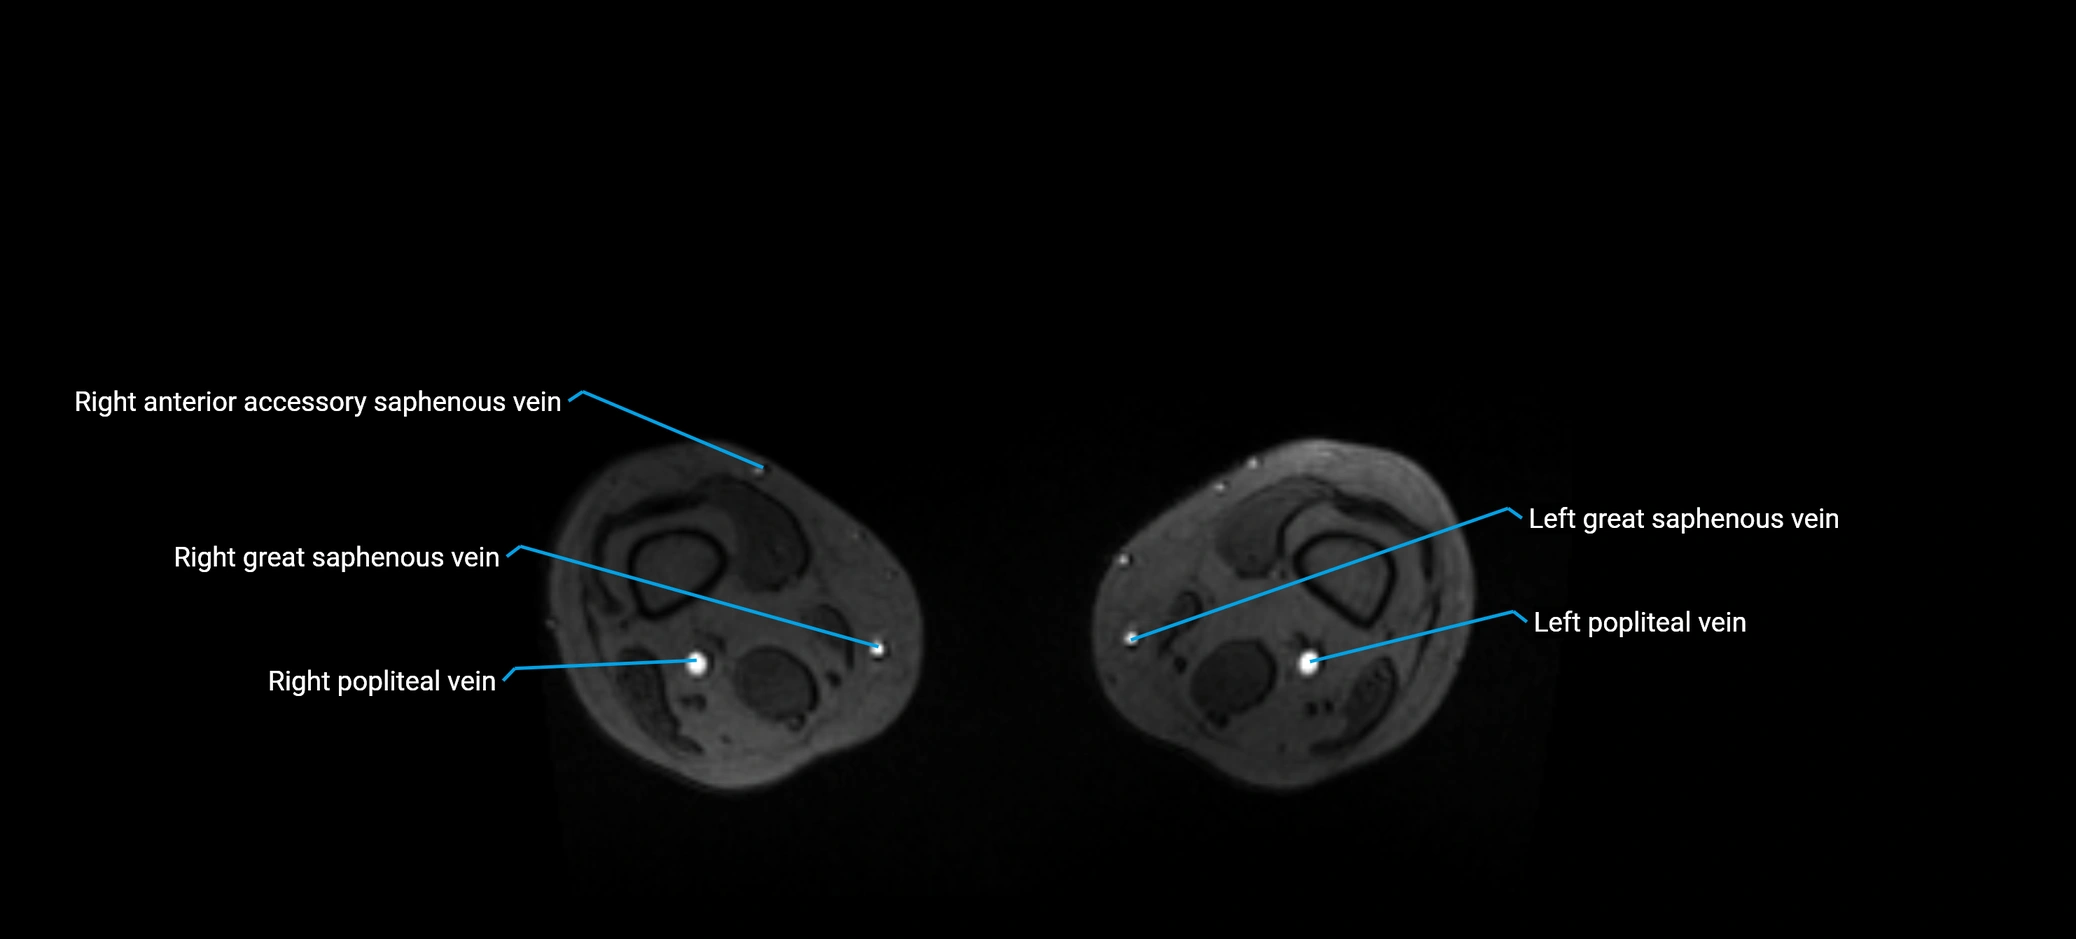

MRI image

image